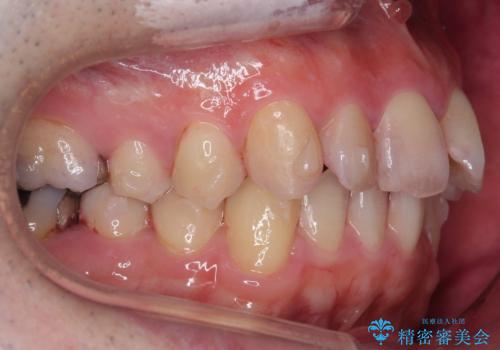

出っ歯と歯のねじれ 非抜歯で 30代男性

右の歯並びが1本分上が前にずれていました。

奥歯のかみ合わせを特に変えず、前歯の並びを整える治療をおこないました。

右上のかみ合わせをそのままにするため、上下の正中は合わない仕上がりとなります。

今回は右のかみ合わせはそのままにしました。左は特に初めから問題ない状態でした。